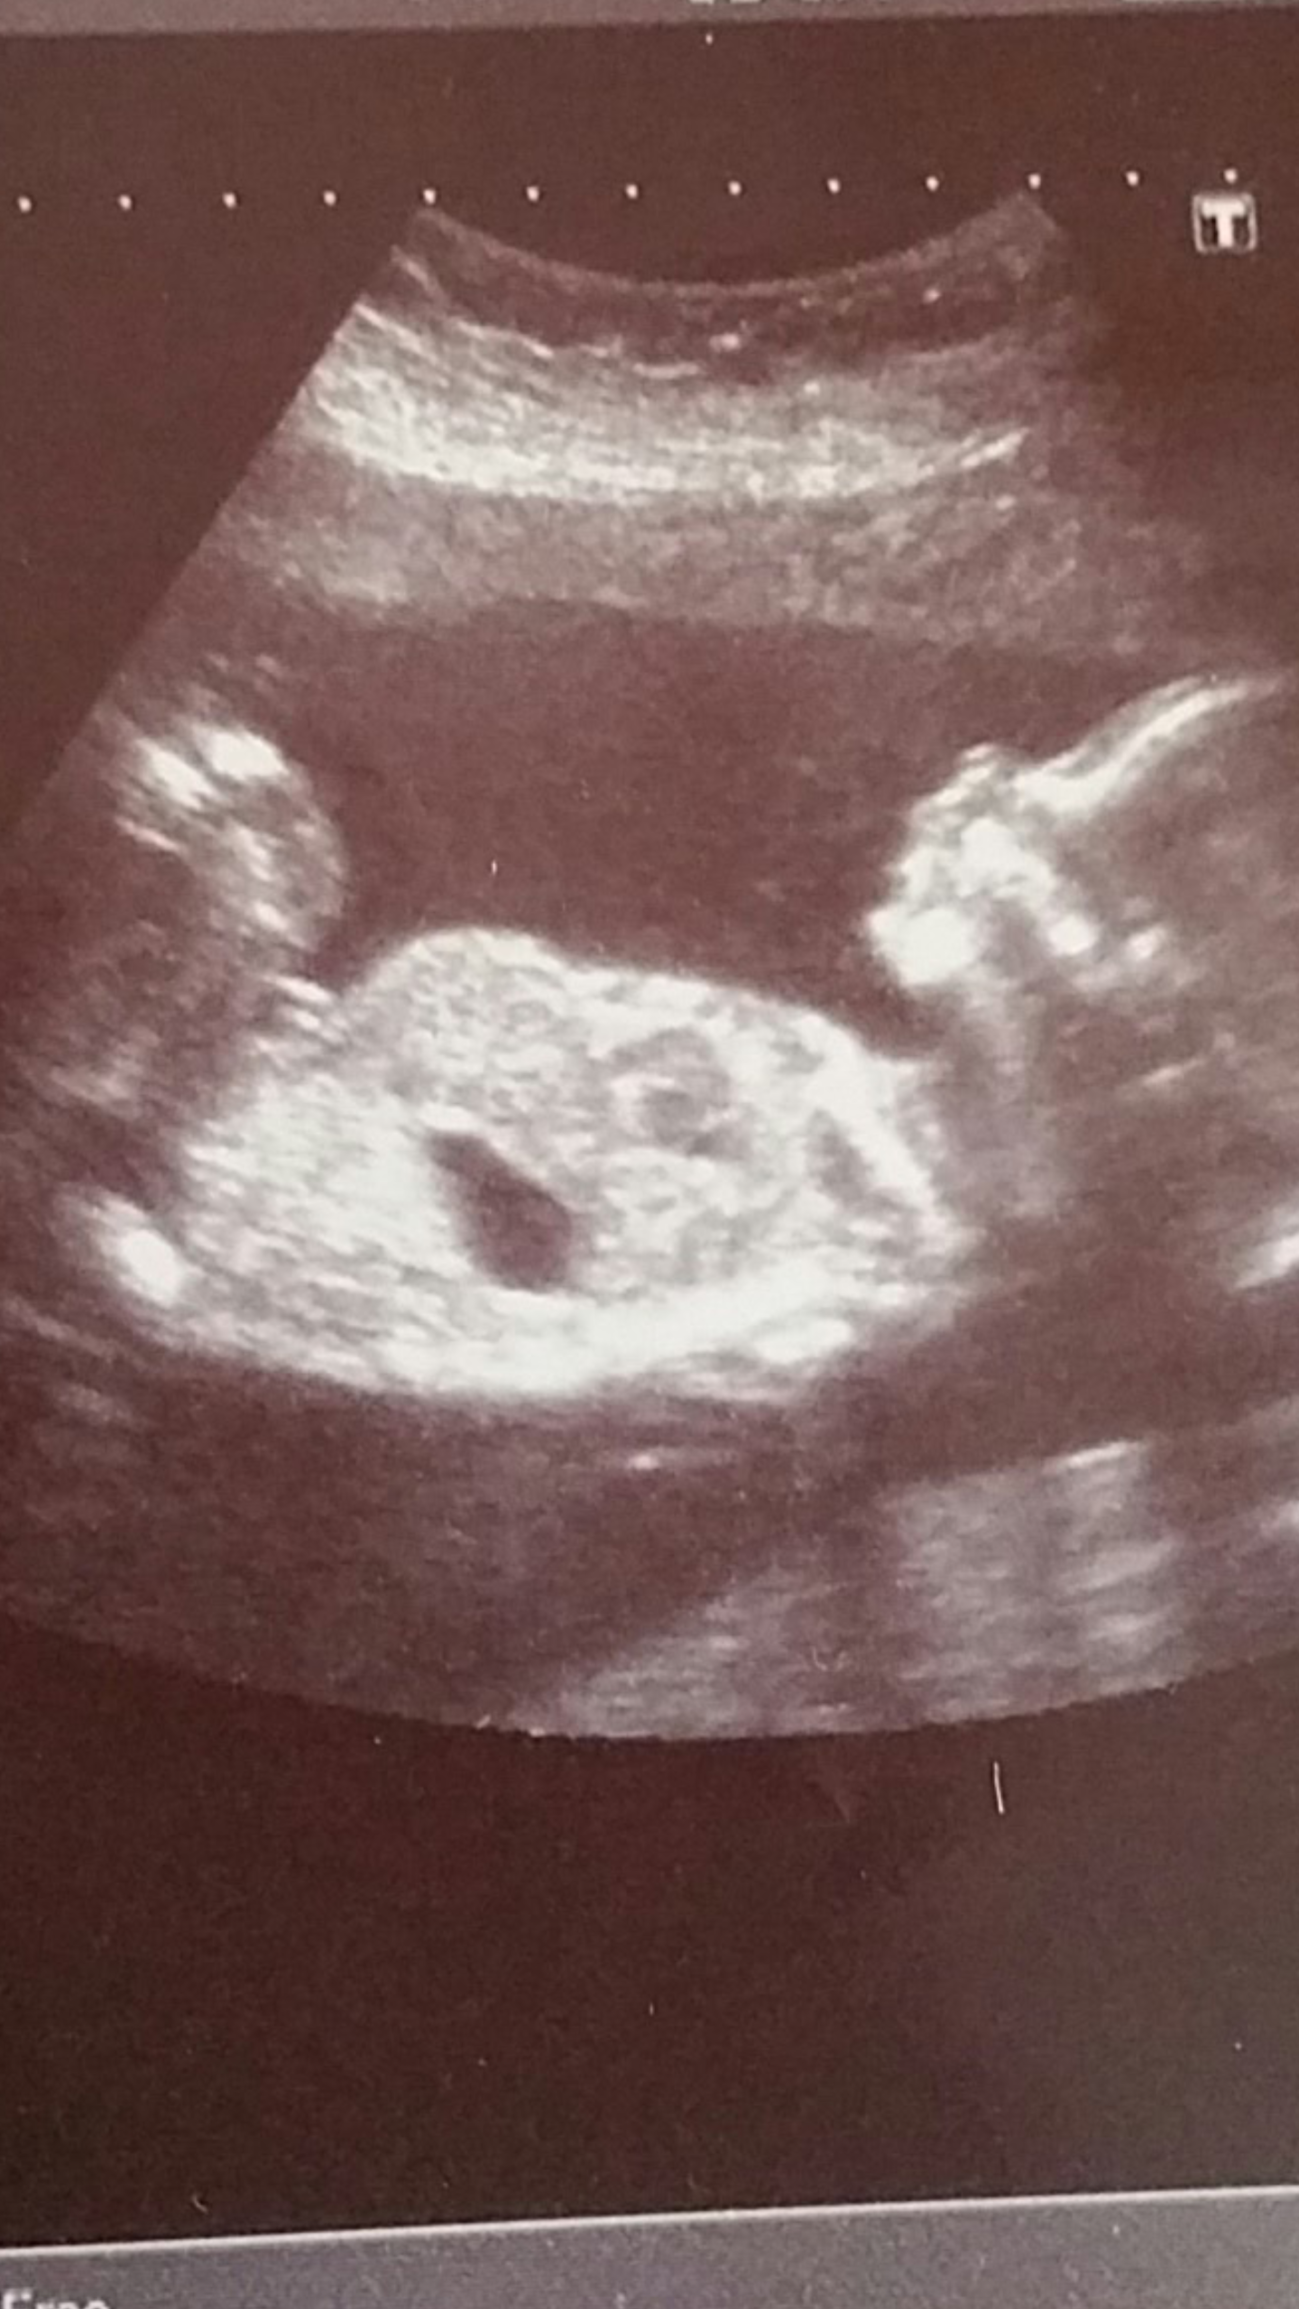

We went to our anatomy scan today and I was sure I saw a penis on the screen but it seemed too big (maybe the umbilical cord?). My husband told me after he thought he saw it too. We have been adamant that we aren't going to find out, so the doctor and technician kept it a secret, but now my curiosity has gotten the better of me. Looking at the picture, I'm thinking I see a penis, or is that something else.....